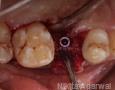

Pictures

Surgery

BONE GRAFT :

Particuled

Autograft: Implant Site

Xenograft: Bio-Oss

MEMBRANE:

Resorbable: Bio-Gide

Yes - Autogenous PRF